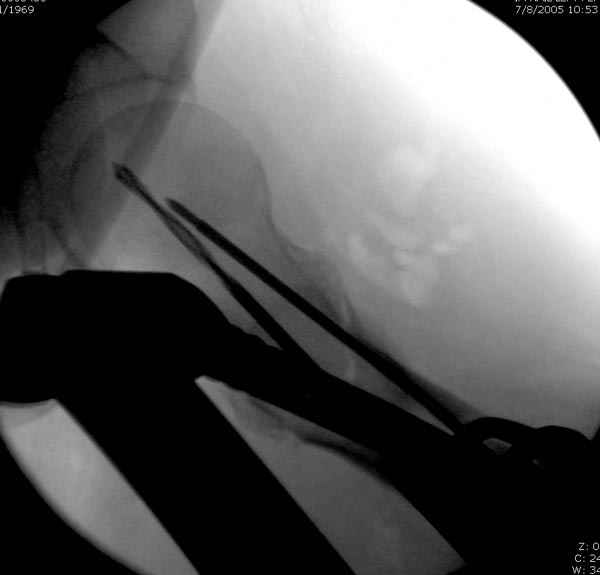

Второй случай тоже репозиция из малого доступа, больному 19 лет, множественные огнестрельные повреждениия конечностей, живота и черепа, правая конечность холодная, без пульсации. Ортопедический диагноз: огнестрельный перелом правого бедра. При срочной ангиографии повреждения сосудов не подтвердилось, конечность из-за ургентности состояния больного зафиксирована временным наружным фиксатором и больной оставлен на операционном столе для срочной лапаротомии хирургической службой.

Больной долго оставался нестабильным, только на 14 день удалось заменить на антеградный интромедуллярный штифт TFN (trochanteric femoral nail) SmithNephew. После неудачной попытки закрытой репозиции, несмотря на использование "joystick", проксимальный стержень от

наружного фиксатора, (перелом начал срастаться) репозицию провели из малого доступа, затем остальные этапы операции.

Случай был представлен из-за того, что больного оперировали после наружной фиксации и был риск инфекцирования через места проведения стержней (на снимках), прошло больше 3 месяцев, выписан из амбулаторной службы из-за отсутсвия надобности дальнейшего наблюдения.